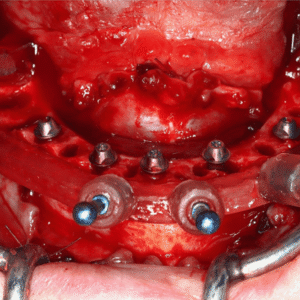

Our experienced faculty, comprised of specialists in implant dentistry, share their insights from years of practical experience, ensuring that you gain not just theoretical knowledge but also real-world applications. By the end of this course, we ensure that participants feel confident and ready to integrate implantology into their own practices.